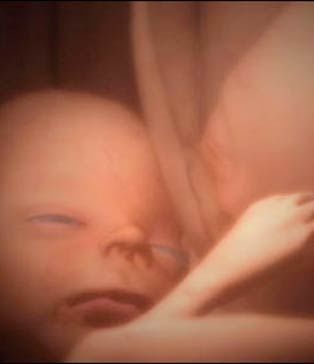

一对双胞胎姐妹中的一个斜靠在另一个身上,还亲了一下对方的脸——这个温馨的画面不是发生在某座大房子里,而是发生在妈妈的子宫里!在英国媒体日公布的一系列照片中,读者能够清晰地看到这些令人震惊的“四维”超声波图像,看到双胞胎和多胞胎是怎样在妈妈的子宫里“玩耍”的。

由于对胎儿进行的是实时拍摄,科学家把这些珍贵的图像称为“四维”图像,他们按照这些图像制作出真实大小的硅树脂模型,并用电脑制作出令人震惊的多胞胎图像。